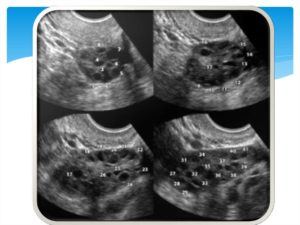

Чтобы подтвердить диагноз, врач вначале, затем в середине и конце менструального цикла назначает УЗИ. Также периодически ультразвук назначают если в процессе данного исследования видны более 10-12 увеличенных фолликулов размером 2-9 мм или яичник, увеличенный в два-три раза.

- Характерная УЗ – картина яичников: наличие более 12 фолликулов в каждом яичнике и/или увеличение объема яичников более 10 мл. Из-за такой особенности их еще называют мультифолликулярные яичники.

При СПКЯ яичники имеют характерную ультразвуковую картину. В них имеется множество мелких фолликулов по периферии яичника, их иногда называют «ожерельем». Обычно это 9-12 фолликулов диаметром до 9 мм. За счет разрастания стромы яичника (ткань которая окружает фолликулы) увеличивается и объем яичников, обычно он более 10 мл.